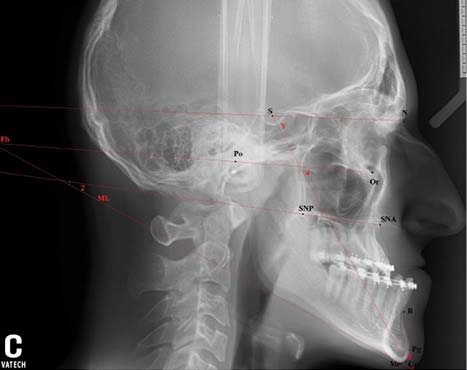

На профильной ТРГ головы, полученной после первого этапа комплексной реабилитации пациента К., изучены те же параметры. Сравнение результатов анализа ТРГ, полученных в начале и конце первого дохирургического этапа ортодонтического лечения (рис. 1, 2) пациента К., показало, что данные краниометрии, в частности ∠SNA, ∠SNB, ∠ANB, угол наклона (∠H) франкфуртской горизонтали (FH) и угол наклона плоскости основания верхней челюсти (∠I) по отношению к плоскости основания черепа (SN), остались неизменными (см. табл. 1, 2).

Рис. 2. Профильная телерентгенограмма головы пациента К.В. 17 лет в конце дохирургического ортодонтического лечения

Обращает на себя внимание изменение наклона окклюзионной плоскости (OcP) в процессе дохирургического ортодонтического лечения. Во время ортодонтической коррекции была получена экструзия первых моляров верхней челюсти, изменены торк резцов, положение клыков и премоляров. В результате устранения промежутков между зубами уменьшилась протяжённость зубных рядов. Вследствие этих изменений изменился наклон окклюзионной плоскости (OcP) относительно оснований челюстей и увеличилось Wits-число (см. табл. 2).

Таким образом, при выборе параметров для анализа профильной ТРГ следует учитывать возможность изменения наклона OcP относительно плоскостей основания верхней (NL) и нижней (ML) челюстей и, как следствие, числа Wits в процессе ортодонтической коррекции положения зубов и размеров зубных дуг.